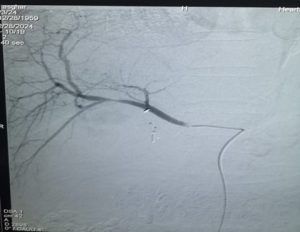

1. A 54-year-old male patient undergoes a laparoscopic cholecystectomy that is complicated by an unrecognised injury to an aberrant right hepatic artery (ARHA). Two weeks post-operatively, the patient presents with the classic Quincke's triad: right upper quadrant pain, obstructive jaundice, and gastrointestinal bleeding (hematemesis/melena) due to a progressive drop in hemoglobin. A subsequent CT angiography and selective angiogram confirm a growing vascular sac communicating with the hepatic artery

What is the most likely diagnosis and its corresponding preferred first-line management?